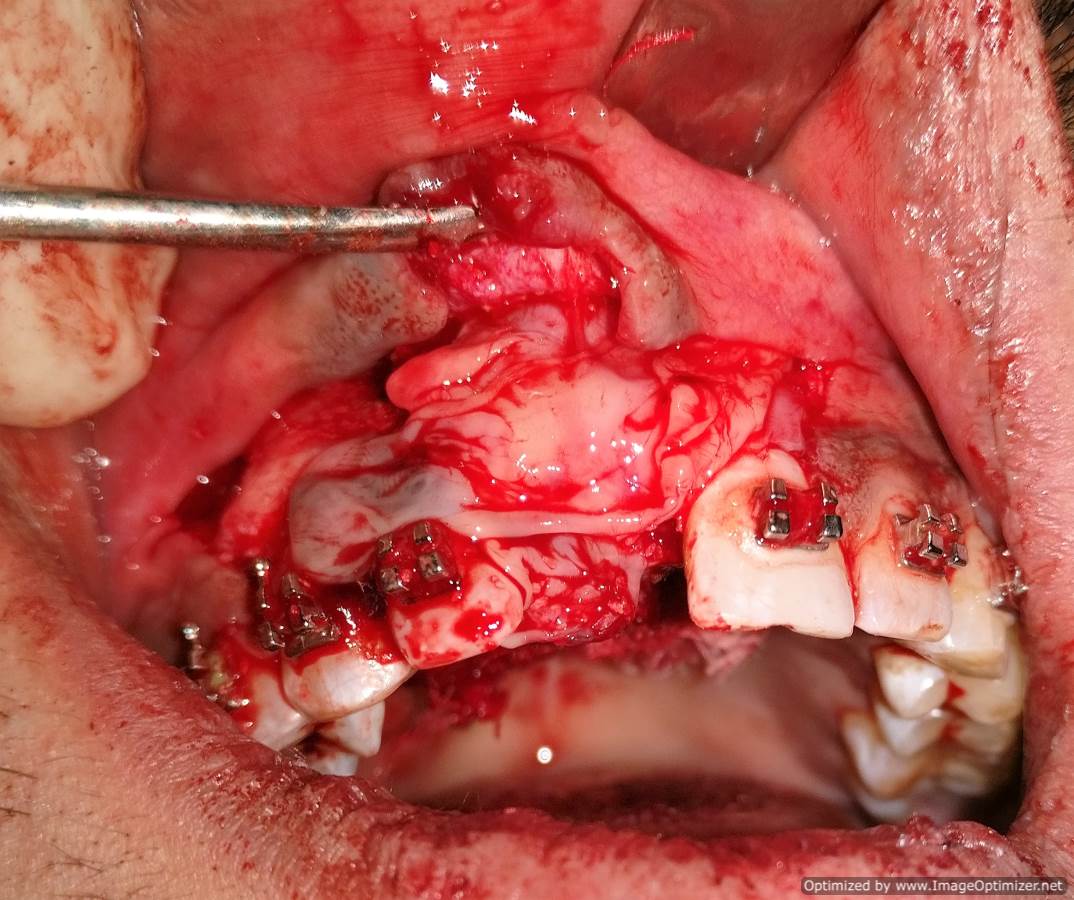

Dental Implant Case Report -03

Home / Case Report / Implant / Dental Implant Case Report -03